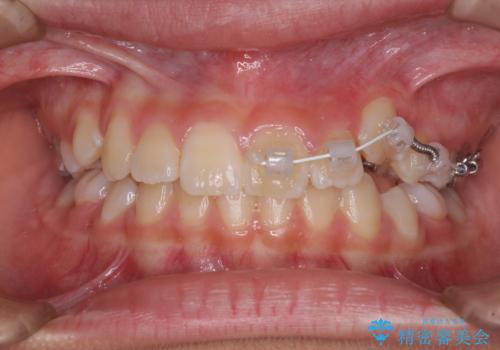

- 小学校での定期歯科検診にて歯列不正を指摘されたとのことで来院された患者様です。

左上の犬歯が低位に埋伏しており、将来八重歯になるリスクが高いと判断されたため、補助装置とワイヤーを用いて犬歯を通常の位置まで移動させることとしました。